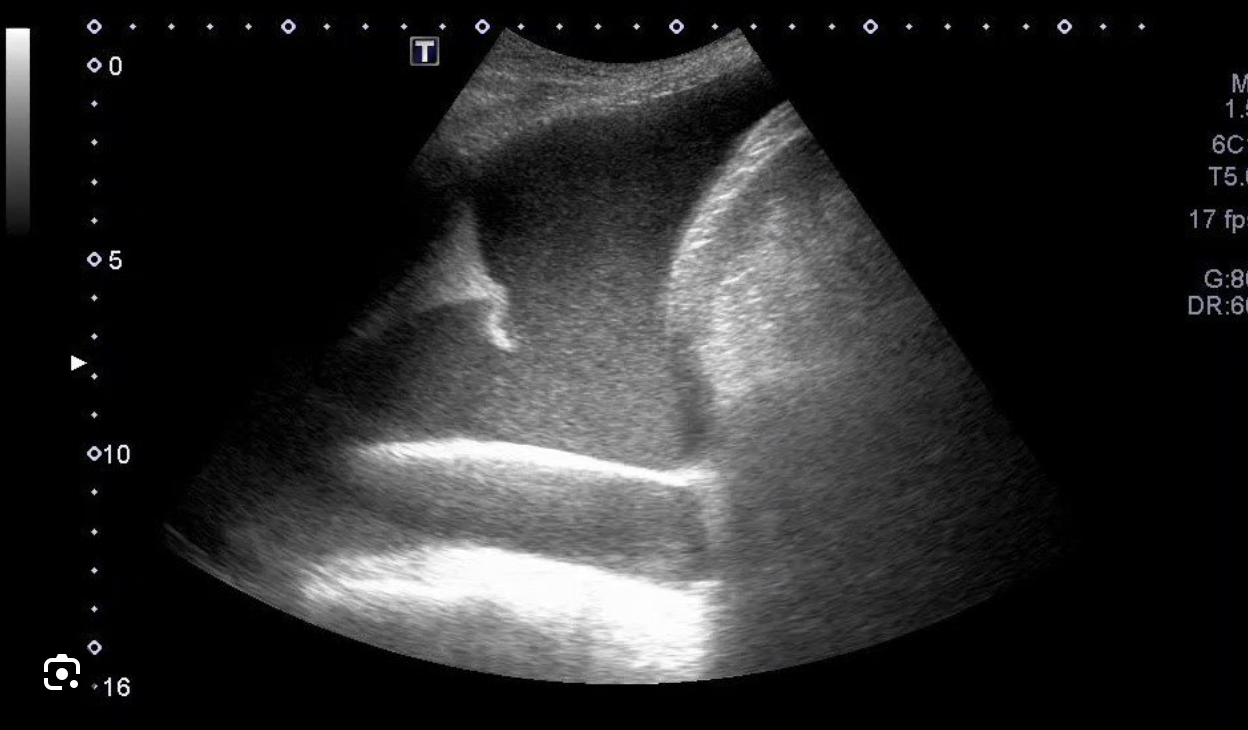

Ecografía pulmonar: mínimo derrame pleural izquierdo sin derrame pericárdico asociado. Sí se detecta derrame pleural derecho, observándose el «signo de la medusa» que se corresponde con una atelectasia completa del lóbulo pulmonar inferior, que flota sobre un derrame pleural masivo.

Por tanto, gracias al estudio con ecografía pulmonar se pudo objetivar una agudización de insuficiencia cardíaca. Descartando otras causas del derrame a través de la clínica y el resto de exploraciones realizadas.